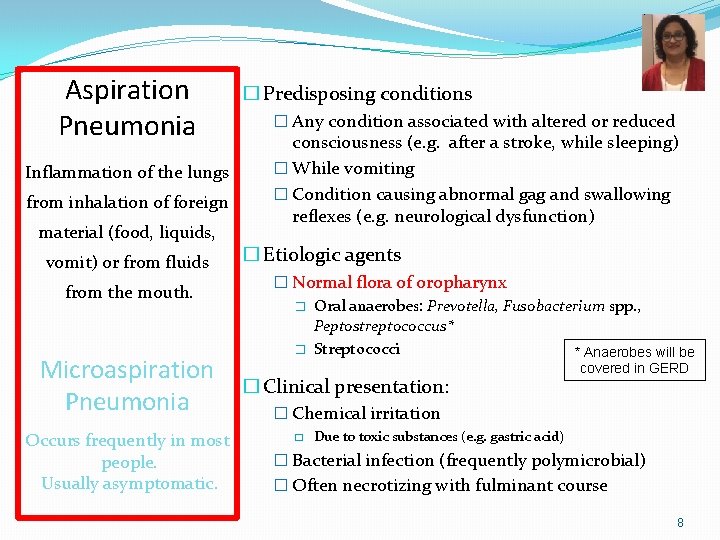

Aspiration Pneumonia Inflammation of the lungs from inhalation of foreign material (food, liquids, vomit) or from fluids from the mouth. Microaspiration Pneumonia Occurs frequently in most people. Usually asymptomatic. � Predisposing conditions � Any condition associated with altered or reduced consciousness (e. g. after a stroke, while sleeping) � While vomiting � Condition causing abnormal gag and swallowing reflexes (e. g. neurological dysfunction) � Etiologic agents � Normal flora of oropharynx � Oral anaerobes: Prevotella, Fusobacterium spp. , Peptostreptococcus* � Streptococci * Anaerobes will be � Clinical presentation: covered in GERD � Chemical irritation � Due to toxic substances (e. g. gastric acid) � Bacterial infection (frequently polymicrobial) � Often necrotizing with fulminant course 8